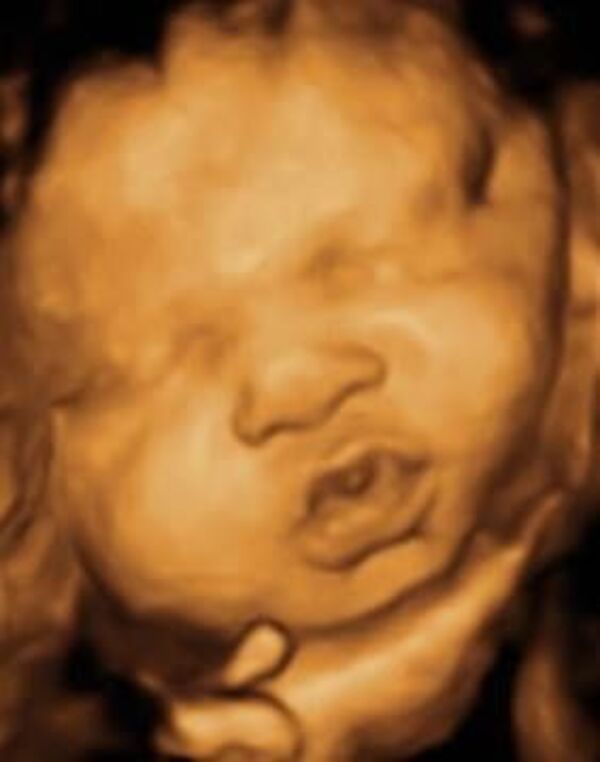

Bebekler anne karnında ne yapar?